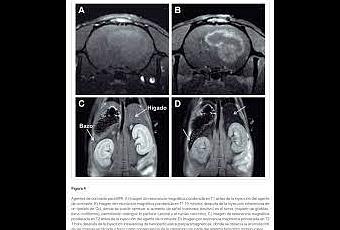

2. Con los agentes de contraste biológicos altamente sensibles desarrollados, la conversión de piruvato en lactato y alanina se demostró con éxito en un modelo animal. Estas conversiones en el metabolismo energético ya se han identificado como marcadores diagnósticos útiles en estudios previos.